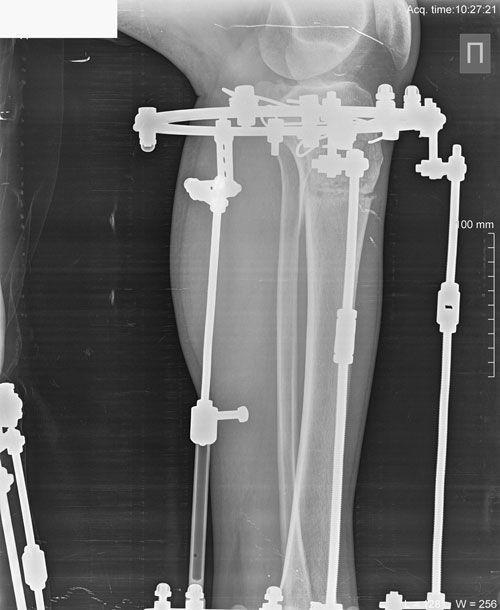

Исходник 38 лет. Алматы.

Дата операции 17.04.2018г.

Рентген в 56 дней.

Сращение идёт отлично!